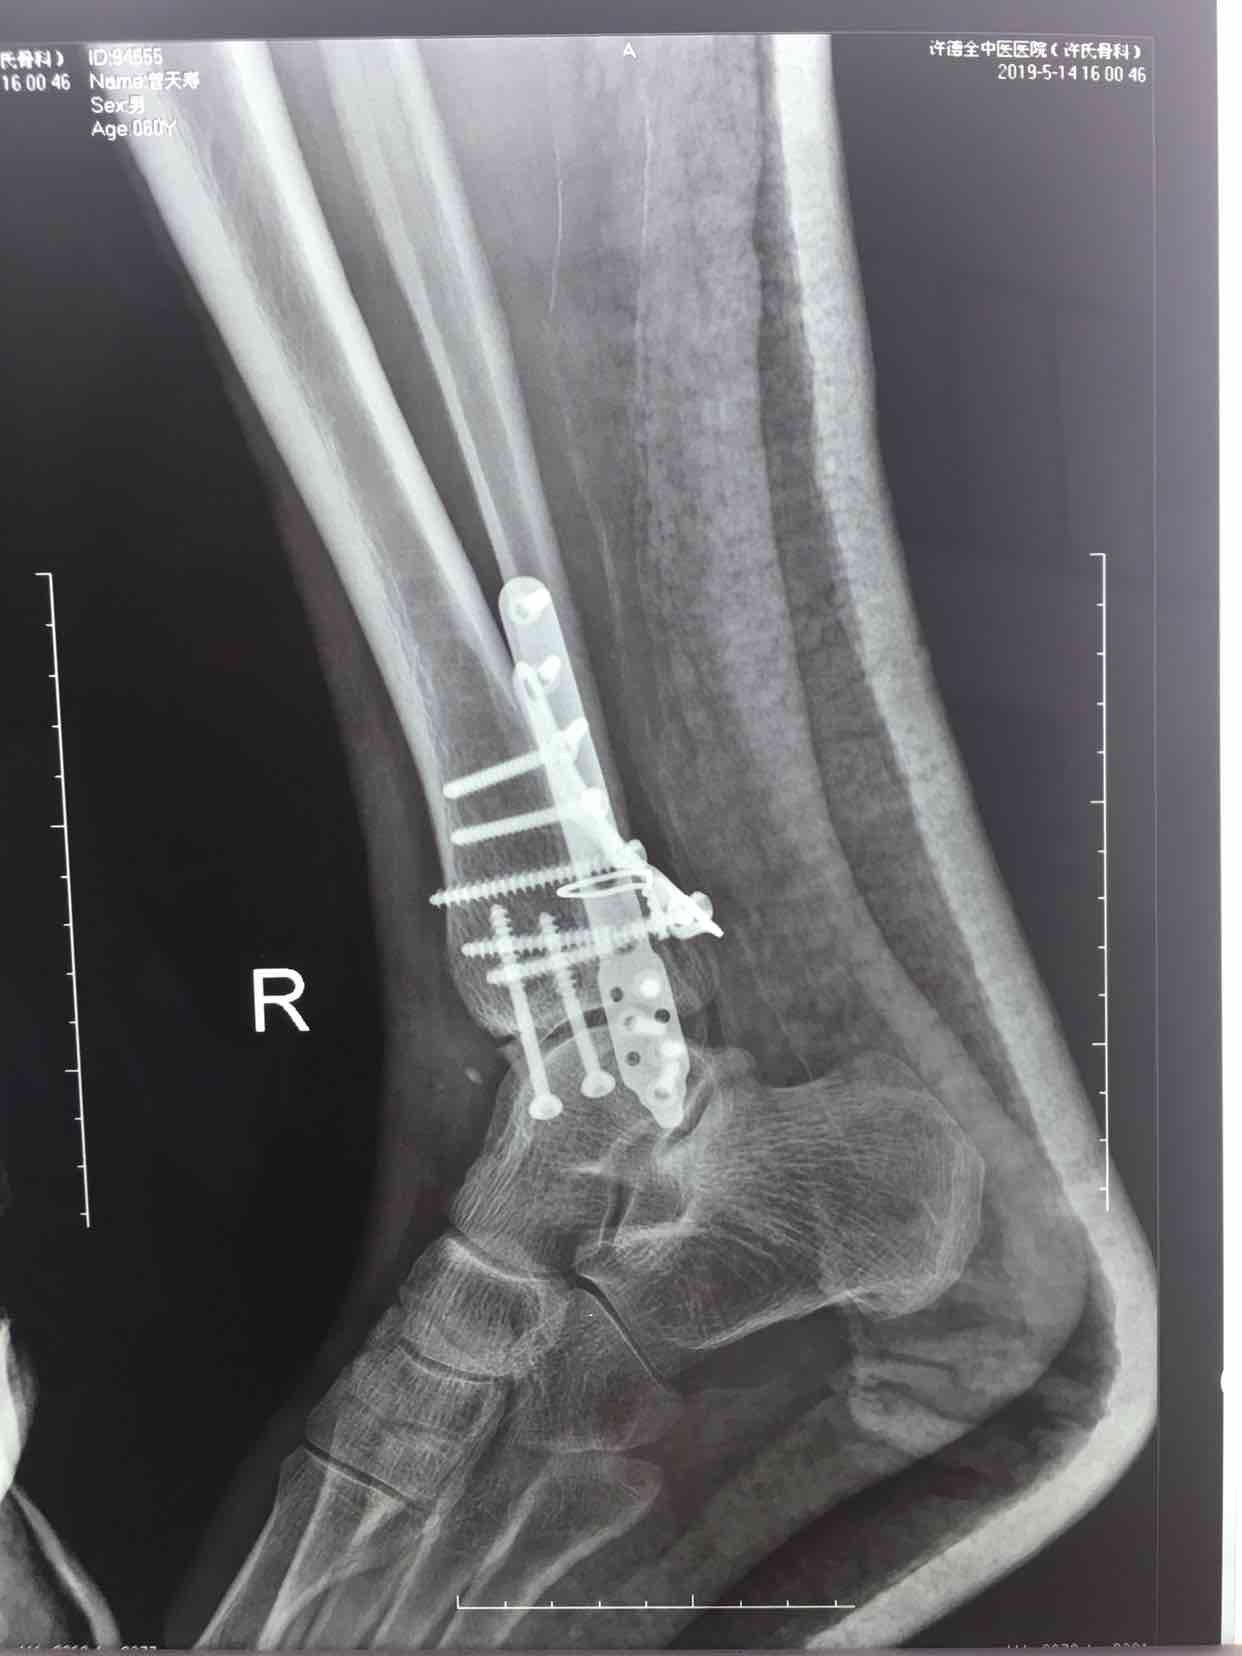

三踝骨折并胫距关节脱位(切复内固定术)

摔伤后右踝肿痛,畸形,活动受限1小时入院。既往身体健康,无特殊不良嗜好。

生命体征平稳,心肺复未见异常。右踝部肿胀,局部皮色发红,皮温高,畸形,压痛及纵叩痛阳性,可及骨擦音或骨擦感,踝关节活动受限,末梢血运感觉正常。

诊断三踝骨折并胫距关节脱位完善术前检查,待肿胀消退后在腰麻下行切复内固定术,术后石膏托固定,抗炎,消肿等处理。